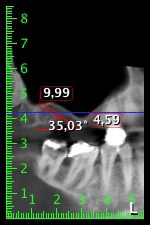

Шест месеца след екстракцията на зъби 16 и 14 се извършва преглед с дигитален томограф (DVT, Planmeca), с цел планиране и намаляване на възможните рискове. Ясно се вижда, че костта не се е регенерирала до желания обем (Фиг. 2 до 7).

Снимки 2 до 7: DVT със силно намален хоризонтален костен обем.

За да ограничим аугментацията до зона 14, след консултация с пациентката, е планирано поставяне на имплант в зона 16, наклонен по посока на челюстта (Фиг. 8).

Този метод изисква винтово фиксиране за финално възстановяване. Необходим е ангулиран абатмънт (например 35°) така, че винтът да бъде перпендикулярен на оклузалната равнина, която позволява мостът да бъде захванат оклузално.

Снимка 8: DVT с план за ъгъла на поставяне на имплант 16